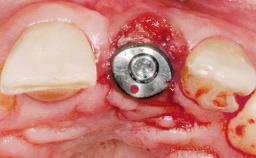

Immediate Placement of an Implant in a Maxillary Left Central Incisor Site

Bone Augmentation Horizontal|Simultaneous

Augmentation Materials Xenogenous|Membrane

Soft Tissue Grafting Simultaneous

Placement Protocol Immediate implant placement